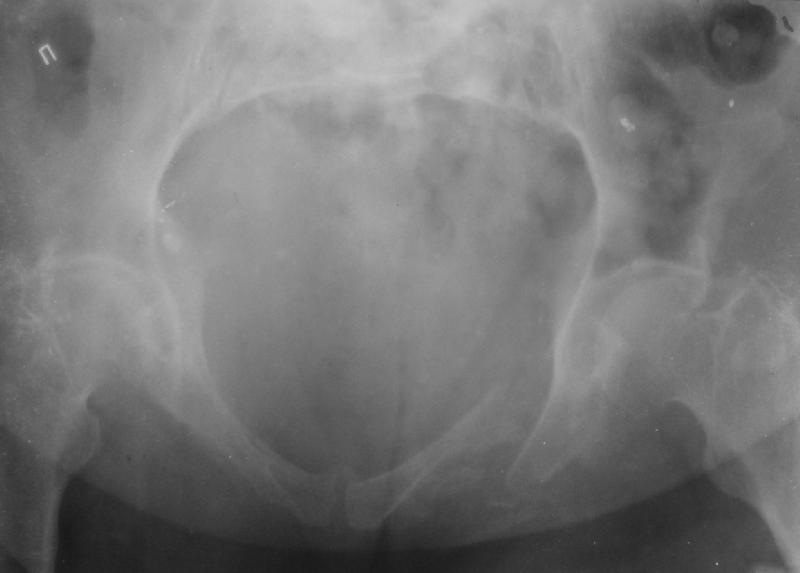

Здравствуйте уважаемые коллеги! Поступила пациентка, 61г, через 1 месяц после травмы, с двусторонним ротационно-нестабильным повреждением тазового кольца: перелом боковых масс крестца с обеих сторон, переломы лонной и седалищной костей слева, отрывные переломы передних остей левой подвздошной кости, сегментарный перелом левой подвздошной кости. Кроме того у пациентки имеется сегментарный перелом левого бедра. Перелом бедра не вызывает вопросов - планируем блокируемый остеосинтез стержнем, а вот при обсуждении тактики лечения переломов костей таза возник вопрос о необходимости синтеза остей подвздошной кости, учитывая сроки с момента травмы и наличие остеопороза могут возникнуть технические сложности. Если у кого-нибудь собственный опыт или ссылки на литературу об отдаленных результатах при не восстановлении сгибательного аппарата бедра?

По поводу перелома боковых масс крестца с двух сторн, мне кажется справа нет повреждения. надо однозначно синтезировать таз, при наличии ЭОПа можно синтезировать лоннуую ксоть одним длдинным винтом, крестец можно так же 2 мя винтами. Перелом крыла подвздошной кости, можно синтезировать на пластинке или так же винтами. Пусть не смущают сроки перелома, синтезировать можно. По поводу перелома бедра, согласен, нужен блокирующий синтез. Вот возникает вопрос. Отсинтезировать бедро, чтоб потом оно не было опорным из-за неадекватной стабилизации таза? Зачам тогда синтезировать?

Уважаемые коллеги, в продолжение обсуждения перелома костей таза с отрывами остей досылаю R-снимки (КТ и КТ с 3d реконструкцией)